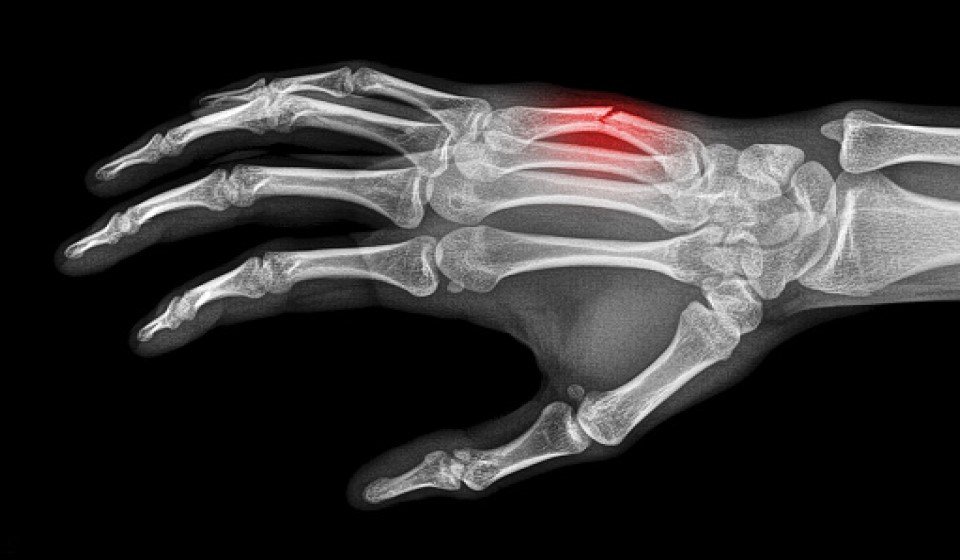

Fratture metacarpali

Dalla diagnosi al trattamento